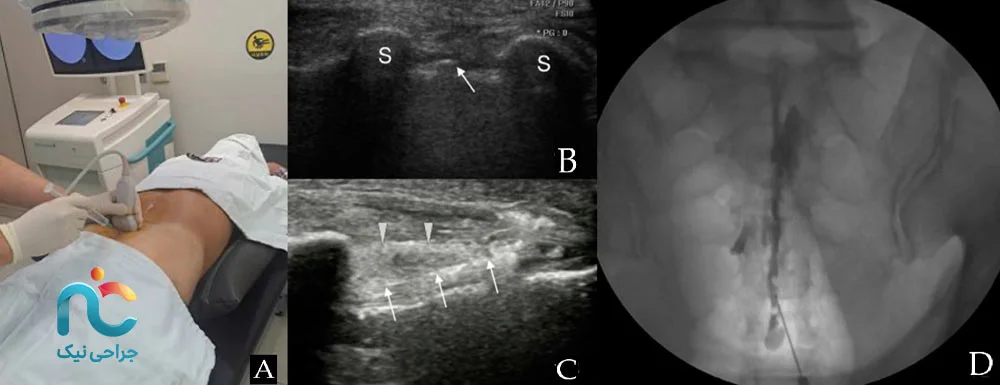

اما خودِ روند انجام تزریق چگونه است؟ این کار در یک مرکز مجهز و در اتاق مخصوص، بهصورت سرپایی انجام میشود. بیمار معمولا روی شکم یا در بعضی شرایط خاص روی پهلو قرار میگیرد و ناحیهی پایین کمر و دنبالچه ضدعفونی میشود و با مقدار کمی داروی بیحسی موضعی، پوست آن ناحیه بیحس میگردد تا هنگام ورود سوزن، درد زیادی احساس نشود. سپس پزشک با کمک دستگاه تصویربرداری (مثل فلوروسکوپی (اشعه ایکس) یا در برخی موارد سونوگرافی)، سوزن را از ناحیهی نزدیک دنبالچه به فضای اپیدورال هدایت میکند و پس از اطمینان از قرار گرفتن در محل مناسب، ترکیب دارویی را بهآرامی تزریق میکند.

تزریق با فلوروسکوپی یا سونوگرافی بهتر است یا بدون تصویربرداری؟

با تصویربرداری همیشه دقیقتر و ایمنتر است، چون پزشک مسیر سوزن و پخش دارو را میبیند. احتمال خطا کمتر و احتمال نتیجه بیشتر میشود. بدون تصویربرداری دقت کمتر است و استاندارد روز دنیا استفاده از روش هدایتشده است.